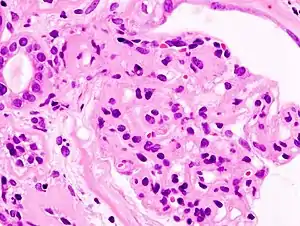

| Microscopic image of diabetic glomerulosclerosis, the main cause of nephrotic syndrome in adults. | |